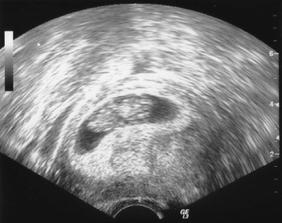

Nasa lasonka 9+2tt

Dnes sme boli na sone a drobcek nam vrtel zadockom a cmulal si palcek 🙂 Bolo to uzasneeee, srdiceko bije ako zvon..najkrajsi zvuk, aky som v zivote pocula 🙂 Budeme mat doma malu tanecnicu 😀 ?!?!?!